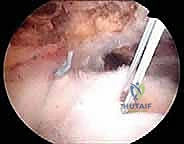

الخطوة 2: الاستكشاف بالمنظار (4K Arthroscopy)

يُحدث الدكتور هطيف 3 إلى 4 ثقوب صغيرة (بحجم ثقب المفتاح). يُدخل كاميرا دقيقة وعالية الوضوح (4K) لاستكشاف المفصل من الداخل. يتم تقييم حجم التمزق، جودة نسيج الوتر، والبحث عن أي إصابات مرافقة (مثل تمزق وتر البايسبس أو التهاب الجراب).

الخطوة 4: زراعة المثبتات وإصلاح مزدوج الصفوف

- الصف الداخلي: تُزرع مثبتات عظمية دقيقة (Anchors) محملة بخيوط جراحية فائقة القوة في الجزء الداخلي من البصمة العظمية.

- تمرير الخيوط: تُمرر هذه الخيوط عبر نسيج الوتر الممزق باستخدام أدوات دقيقة.

- الصف الخارجي: تُسحب الخيوط لتغطية الوتر فوق العظم، ثم تُثبت باستخدام مثبتات عظمية أخرى في الجزء الخارجي، مما يخلق شبكة محكمة تضغط الوتر بقوة ضد العظم.